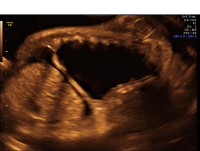

Hydrops

Hydrops fetalis, or hydrops, is a condition in which fluid accumulates in different parts of the fetal body. There are two types: immune and non-immune. The immune type is caused by destruction of fetal red blood cells by the mother’s immune system. The non-immune type is more common and has a variety of causes, including viral infections, heart or lung abnormalities, and genetic conditions. Non-immune hydrops occurs in one in 1,500 to 4,000 births. Although an exact rate is unknown, immune hydrops is rare.